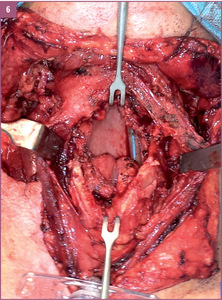

Zaplanowanie, wytworzenie, kształtowanie oraz implantacja zmodyfikowanego mikronaczyniowego płata małżowiny usznej opartego na naczyniach skroniowych.

A.M.: Tak, wspólnie uznaliśmy, że opracowanie takiej metody byłoby bardzo skuteczne i pomocne dla cierpiących na średnio lub wysoko zaawansowaną chorobę nowotworową nagłośni lub też średnio zaawansowanego raka krtani obejmującego nagłośnię. Doszliśmy do wniosku, że skoro do tej pory stosowano wiele nieskutecznych metod, nadszedł czas na wykorzystanie trójwymiarowej struktury odpowiadającej nagłośni i pochodzącej z ludzkiego ciała. Założyliśmy więc, że możemy wykorzystać zmodyfikowany fragment małżowiny usznej na naczyniach skroniowych z elementami skóry okolicy przed-, za- i nadusznej. Chodziło nam o to, by te elementy skórne odtwarzały boczne ściany gardła i część górną krtani, która również jest resekowana w przypadku raka nagłośni. Fragment małżowiny usznej z chrząstką w środku mógłby zatem po modyfikacji stanowić element elastyczny odpowiadający kształtowi i wielkości nagłośni. Liczne zabiegi przeprowadzone na zwłokach utwierdziły nas w przekonaniu, że wykonanie takich rekonstrukcji jest możliwe. Po kwalifikacji i przygotowaniu chorych na raka nagłośni w stopniu zaawansowania T2 i T3 z naciekiem na nasadę języka (nie większym niż 1-2 cm, gdzie kończy się możliwość rozsądnej rekonstrukcji), postanowiliśmy wykorzystać tę właśnie technikę.

CHARAKTERYSTYKA PRZYPADKU